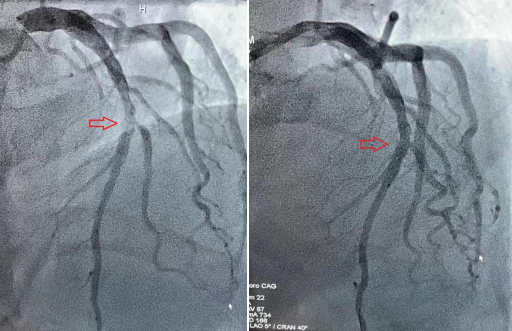

血管开通前 血管开通后

无独有偶,在雷先生刚刚下手术台不久,又一名50余岁的男性胸痛患者入院,急查心电图提示急性下壁心肌梗塞,李主任顾不上休息,带领介入团队再次上场。这次是患者血管被一个巨大的血栓堵死,在反复的血栓抽吸后,血管再次恢复了通畅。从患者进医院大门到血管开通仅仅用了不到一个小时,患者就被医护人员从死亡线上拉了回来,时间远远低于全国平均水平。